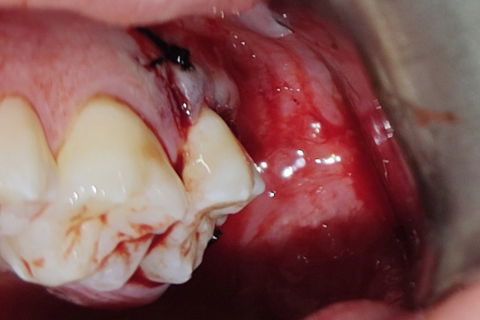

Leito cirúrgico após as exodontias

Paciente B. F. L. , compareceu ao meu consultório relatando dores na região dos dentes do siso apesar de estarem inclusos, paciente relatava bastante "pressão" na região e nos dentes. Outra queixa era a ausência do segundo molar inferior do lado esquerdo. Foi realizado consulta, anamnese, paciente "ASA1" solicitação de raio-x panorâmico. Após avaliação do raio-x panorâmico observei que o paciente possuía os dentes 18, 28, ,37 38, 48 inclusos/impactados. Os terceiros molares apresentavam-se mesio-angulados quase horizontais. Após planejamento cauteloso, foi realizado a remoção dos 5 dentes inclusos em uma única etapa cirúrgica. Observem nas imagens que a incisão "relaxante" na região cirúrgica dos dentes 37 e 38, foi realizada na mesial do dente 35 (isso para que se haja um bom afastamento do retalho para melhor visualização e acesso). Foi passado as medicações pós cirúrgicas para o paciente e nesse caso o corticóide foi receitado, para evitar edemas devido grande acesso cirúrgico; além do antibiótico, antiinflamatório e analgésico (gosto muito de receitar o toragesic).